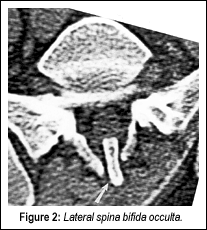

Spina bifida occulta can involve one or several adjacent vertebral segments, most commonly the transitional levels of the spine. It most often involves the first sacral segment, where it is associated with absence of the spinous process (SP) or lamina, or both. The unattached spinous process, if there is one, may remain in place, held by the ligamentum flavum, or it can fuse with the L5 SP to form a hooked or "tongue-shaped" process pointing toward the defect in the spinal canal. The L5 SP can also be unusually large (it is normally smaller than those of the other lumbar segments), and in the absence of the S1 SP, may protrude into the defect. All these situations are termed the "clasp-knife deformity," as described by Henry, et al.2

The intraspinal pathological changes associated with spina bifida occulta have been reported; upon surgery, the histologic abnormalities consist of fatty and fibrous tissue in contact with the nerves of the cauda equina, and often completely enveloping them. The dura is often incomplete or poorly formed at the level of the posterior arch defect. In extension, the L5 SP can encroach on the spinal canal.

I will demonstrate one case where this was a definite factor in a patient's lower back pain. A 28-year-old male developed lower back pain at the age of 19 while lifting heavy boxes. He had intermittent recurrences of lower back pain since the initial episode. He described the pain as "pins and needles" in the base of his back. The pain radiated to the left hip, with associated intermittent numbness in the left calf. Symptoms were aggravated by standing and physical activity, and were relieved by lying down. He had no pain at night, but did complain of morning stiffness. Neurological examination revealed absent Babinski signs bilaterally, and diffuse, mild tenderness over the lower lumbar spinous processes and paraspinal muscles. Anterior-posterior (Figure 1) and lateral views (Figure 2) demonstrated spina bifida occulta at the S1 segment associated with an elongated L5 SP. Computerized tomography (CT) revealed spina bifida occulta, the classic clasp-knife deformity, with encroachment upon the spinal canal (Figure 3).